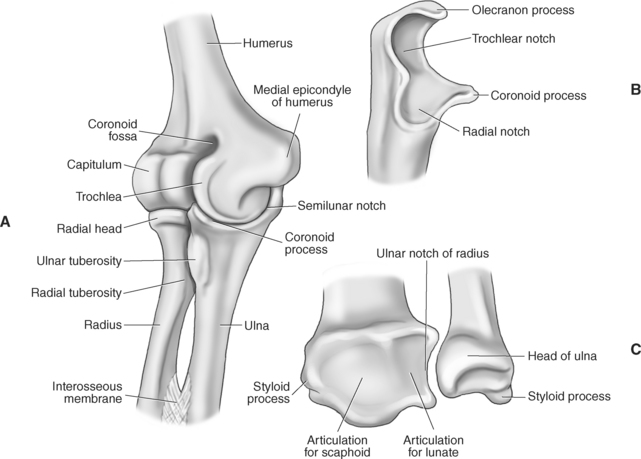

The elbow is a complex hinge-pivot joint created by the articulations of the humerus, radius, and ulna. All three articulations communicate with each other within a single joint capsule. The radius and ulna are the bones of the forearm, with the radius located on the lateral side. The radioulnar and radiohumeral articulations create the pivot joint that aids in supination and pronation of the elbow. The radiohumeral and ulnohumeral articulations form the hinge joint that allows for flexion and extension (Figures 9.70 through 9.73).

Figure 9.73 Anatomy of the elbow and distal forearm. A, Elbow in medial view. B, Proximal ulna in lateral view. C, Distal radius and ulna.

The distal portion of the humerus has two distinct prominences termed the medial and lateral condyles, with associated epicondyles, that provide attachment sites for tendons and ligaments (Figure 9.70). The medial epicondyle serves as the site of origin for the common flexor tendon, pronator teres muscle, and medial collateral ligament, whereas the lateral epicondyle serves as the attachment site for the common extensor tendon, supinator muscle, and lateral collateral ligament. Just lateral to the medial epicondyle along its posterior surface is a shallow groove containing the ulnar nerve. Two depressions located on the distal humerus are the anterior coronoid fossa and the deep posterior olecranon fossa. These depressions accommodate the coronoid and olecranon processes of the proximal ulna (Figures 9.70, 9.71, and 9.73). The distal humerus has two cartilage-covered articular surfaces—the capitellum and the trochlea for articulation with the radius and ulna (Figure 9.71). The lateral of the two surfaces is the capitellum, a rounded projection that articulates with the concave surface of the radial head. The trochlea is more medial and has the appearance of an hourglass if viewed in the horizontal plane. The shape of the trochlea helps keep the ulna in position during flexion between the distal humerus and proximal radius (Figure 9.73).

The radius is a long, slender bone with a proximal portion that consists of the radial head, neck, and tuberosity. The radial head has a flat cartilage-covered depression or fossa (fovea of the radius) that articulates with the capitellum of the humerus. In addition, the articular circumference of the radial head articulates against the radial notch of the ulna during supination and pronation. The radial head is attached to the body of the radius by the narrow radial neck. Located at the distal portion of the neck on the medial side of the radius is a roughened projection termed the radial tuberosity. The radial tuberosity serves as the attachment point for the biceps brachii muscle (Figures 9.72 through 9.74).

The ulna is located medial within the forearm. The proximal ulna consists of the olecranon and coronoid processes and the trochlear and radial notches. The superficial dorsal surface is formed by the hook-shaped olecranon process, which is the attachment site for the triceps brachii. The trochlear notch is a half-moon-shaped concave articular surface that curves around the trochlea of the humerus. This articulation allows for flexion and extension of the elbow. Located on the anterior portion of the distal end of the trochlear notch is a small beaklike process called the coronoid process. Just distal and lateral to the coronoid process is a flattened depression called the radial notch. It is covered by articular cartilage for articulation with the radial head. Immediately distal to the coronoid process is a roughened bony surface termed the ulnar tuberosity. The tendon of the brachialis muscle inserts on both the coronoid process and the ulnar tuberosity (Figures 9.72, 9.73, 9.75, and 9.76).

The smaller, distal end of the ulna has two prominent projections. The larger, rounded projection is an articular eminence termed the head of the ulna. It articulates with the ulnar notch of the radius and the triangular fibrocartilage complex. The small conical projection on the medial surface is called the ulnar styloid process, which serves as the attachment site for the ulnar collateral ligament of the wrist. Another structure that is important in stabilizing and strengthening the connection between the radius and ulna is the interosseous membrane, a strong fibrous sheath stretching between the interosseous borders of both bones (Figure 9.72, A and B).